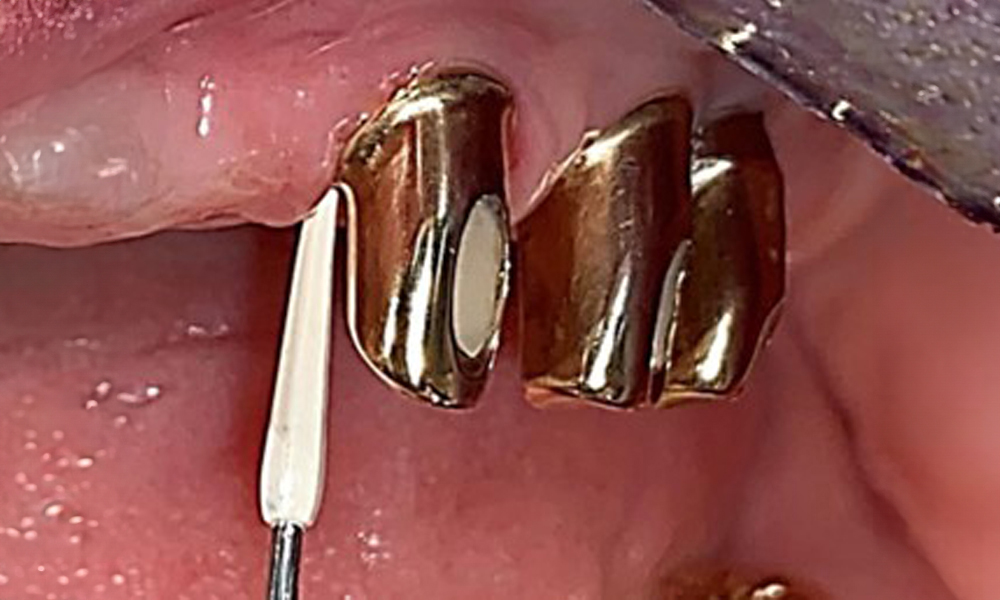

Die Patientin wurde vor über 25 Jahren mit einer kombinierten herausnehmbare Implantat-Teleskopprothese im Oberkiefer versorgt (Abb. 1, Abb. 2, Abb. 3) und ist sehr glücklich über ihren Zahnersatz. Im Unterkiefer hat die Patientin einen suffizienten festsitzenden Zahnersatz. (Abb. 4)

Der dentale Befund stellt sich wie folgt dar: Kombinierte herausnehmbare Implantat- und zahngetragene Teleskoparbeit auf Implantaten 15, 13, 21, 23, 24, 25 und Zahn 11 (Abb. 1, Abb. 2, Abb. 3). Im Unterkiefer ist die Patientin mit einem festsitzenden Zahnersatz versorgt. 37–34 sowie 45–47 haben suffiziente Brücken (Abb. 4). Kronenränder sind intakt, aktive kariöse Läsionen sind nicht vorhanden. An Zahn 43 zeigt sich eine Compositefüllung mit Randspalt. Im Unterkiefer liegen Rezessionen mit freiliegender Wurzeloberfläche zwischen 1 – 3 mm vor. Dies trifft auch für 11 zu.

Für die Entfernung von Zahnstein und Konkrementen am natürlichen Zahn kann Schall Ultraschall verwendet werden sowie konventionelle Handinstrumente (8). An den Implantaten sind für mineralisierte Beläge Titan- oder Kunststoffküretten (Abb. 10) einzusetzen oder ein Kunststoff- bzw. Peek-Ansatz (Abb. 11) für die Ultraschallbehandlung, um die Implantatoberfläche nicht zu beschädigen.